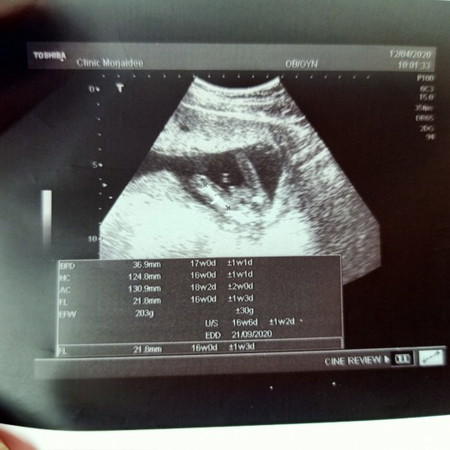

ทำไมเรา 4เดือนกว่าแล้ว น้ำหนักยังไม่เพิ่มเลยคะ ลดไป2กิโลเลย แถมท้องไม่ใหญ่ด้วย. หมอบอกเหมือนไม่ได้ท้องเลย คนไปตรวจนั่งข้างกัน 5เดือน เค้าท้องใหญ่มาก. กังวลมากเลยค่ะ ซาวแล้ว เพศ ชาย คลอด 21กันยานี้ค่ะ #ท้องแรก

เหมือนกันเลยค่ะ ก่อนท้องน้ำหนัก 50ตอนนี้เหลือ47 แล้วค่ะ กำหนดคลอด 21 กันยายน นี้ค่ะ ท้องไม่มีเลยค่ะ 17 สัปดาห์ 4 วันแล้วค่ะ แต่ยังไม่อัตราซาว